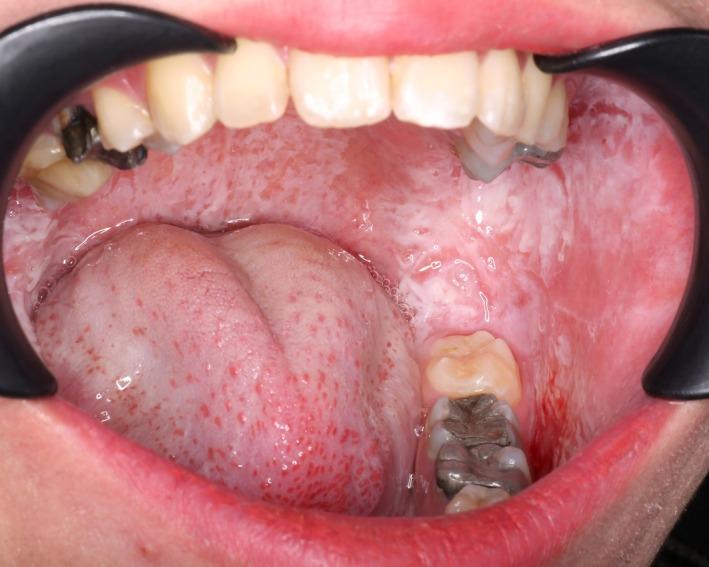

口腔白色海绵状痣:一例罕见病例报告。

Oral White Sponge Nevus: A Rare Case Report.

White sponge nevus (WSN) is a rare, benign genetic disorder characterized by distinctive white or gray mucosal lesions, most commonly affecting the oral cavity. Inherited in an autosomal dominant pattern, WSN results from mutations in keratin genes-primarily KRT4 and KRT13. These mutations lead to the development of thick, spongy plaques in the oral mucosa, with extraoral involvement more commonly associated with KRT13 mutations. The condition typically manifests in early childhood, presenting as painless, persistent white plaques. Diagnosis is usually based on clinical evaluation, although histopathological examination can provide confirmation. WSN is generally asymptomatic and does not require treatment; however, its cosmetic appearance may cause psychological discomfort. Although malignant transformation is rare, certain antimicrobial therapies have shown promise in symptom management. This report describes a case of WSN in a 23-year-old Iranian woman, detailing the clinical presentation, diagnostic process, and potential treatment strategies. Despite its benign nature, further research into the pathogenesis and therapeutic options is essential to improve patient care and quality of life.

摘要

白色海绵状痣(WSN)是一种罕见的良性遗传性疾病,其特征为独特的白色或灰色黏膜病变,最常累及口腔。WSN以常染色体显性模式遗传,由角蛋白基因(主要是KRT4和KRT13)突变引起。这些突变导致口腔黏膜出现增厚的海绵状斑块,口外受累更常与KRT13突变相关。该病通常在儿童早期出现,表现为无痛性、持续性白色斑块。诊断通常基于临床评估,不过组织病理学检查可提供确诊依据。WSN一般无症状,无需治疗;然而,其外观可能会引起心理不适。虽然恶变罕见,但某些抗菌疗法在症状管理方面已显示出前景。本报告描述了一名23岁伊朗女性的WSN病例,详细介绍了临床表现、诊断过程及潜在治疗策略。尽管其本质为良性,但进一步研究发病机制和治疗选择对于改善患者护理和生活质量至关重要。